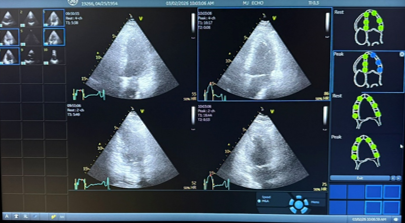

Ultrasound images are obtained before and immediately after exercise.

- Ultrasound images of the heart are taken before exercise and immediately after walking on the treadmill. By comparing these images, we can identify areas of the heart muscle that may not be receiving adequate blood flow from the coronary arteries.

Stress echocardiogram images help evaluate blood flow to the heart muscle.